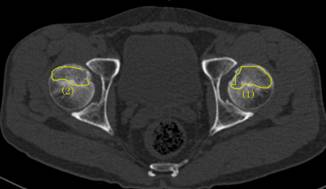

37歲的患者吳先生反復(fù)雙髖疼痛2月余,聽說瀘州市中醫(yī)院在治療骨科疾病方面很有經(jīng)驗(yàn),遂來到醫(yī)院治療。經(jīng)檢查,吳先生雙側(cè)股骨頭壞死(II期),如不及時(shí)進(jìn)行手術(shù)治療,他的股骨頭將進(jìn)一步壞死至骨頭塌陷,引發(fā)關(guān)節(jié)炎,嚴(yán)重時(shí),必須行關(guān)節(jié)置換術(shù)。這樣,將會(huì)給吳先生的生活質(zhì)量及經(jīng)濟(jì)帶來嚴(yán)重負(fù)擔(dān)。

術(shù)前報(bào)告顯示患者雙側(cè)股骨頭壞死